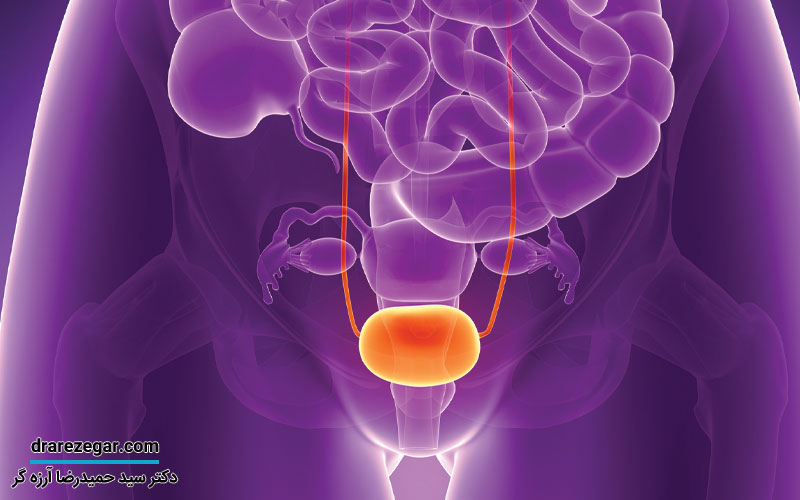

مثانه عهده دار عملکرد اساسی نگه داری و تخلیه ادرار است، که در قسمت پایینی شکم واقع شده و ادرار را از کلیه ها جمع آوری و نگه می دارد. وقتی مثانه پر می شود، عصب های مثانه نیاز به تخلیه ادرار را به مغز ارسال می کنند. بیماری های مرتبط با مثانه شامل عفونت های مجاری ادراری، عفونت مثانه، سرطان مثانه، بی اختیاری ادرار، سنگ مثانه و اختلالات دیگر هستند.

بیماری های مثانه می توانند از عفونت های جزئی تا بیماری های جدی تر و حتی سرطان شامل گردند. در زیر شایع ترین بیماری های مثانه و علل احتمالی آنها را بررسی می کنیم.

سرطان مثانه به رشد یک بافت غیر طبیعی در دیواره مثانه که با تقسیم سلول ها به طور غیرمعمول و مهارنشده همراه است، اشاره دارد. این نوع سرطان می تواند خوش خیم یا بدخیم باشد. در صورتی که بدخیم باشد، ممکن است به گره های لنفاوی، استخوان، کبد و ریه ها گسترش یابد. این بیماری در افراد بالای ۵۰ سال شایع تر است و به طور کلی در مردان بیشتر از زنان دیده می شود.